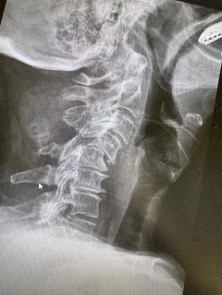

89 years old Patient had a car accident in London, she developed unstable dislocated neck fracture C4/5. We carried out stabilisation and she was able to ambulate on day 1 after surgery.